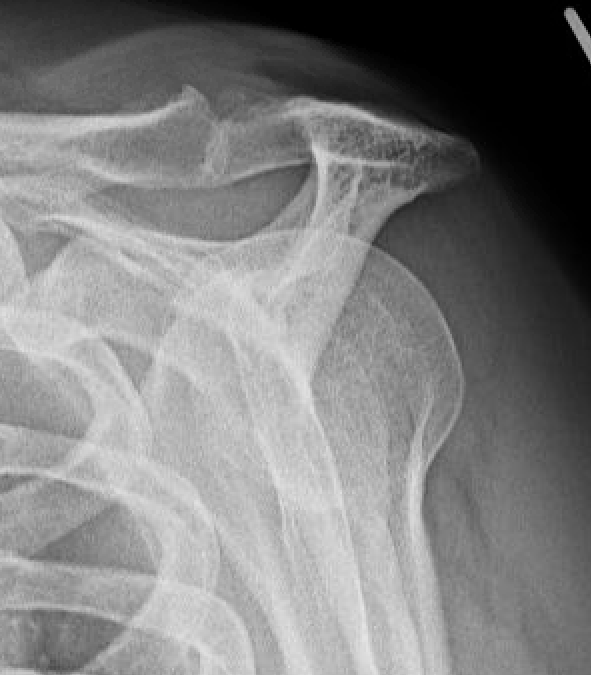

Acromial Morphology

Bigliani / Assess on Supraspinatous Outlet View / Scapula Lateral

| Type 1: Flat | Type II: Curved | Type III: Hooked |

Andrea et al Skeletal Radiol 2024

- 850 patients with suspected shoulder impingement

- type III in 16%

- meta-analysis of acromial morphology and rotator cuff tears

- type III acromial spurs associated with rotator cuff tears

- type I and II are not

Type III acromial spur associated with a full thickness rotator cuff tear

X-ray

| AP | Supraspinatus outlet view | Axillary lateral |

|---|---|---|

|

Sclerosis greater tuberosity / acromion Lateral Acromion spur |

Acromial morphology | Os acromiale |